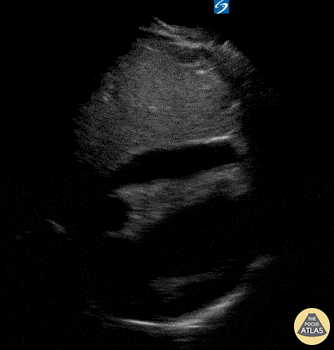

Pericardial Disease - Subxiphoid View of Pericardial Effusion

Seen here is a subxiphoid view of a circumferential pericardial effusion. Of note, there is no diastolic RV collapse, therefore no echocardiographic tamponade. Moudi Hubeishy @moudihubeishy